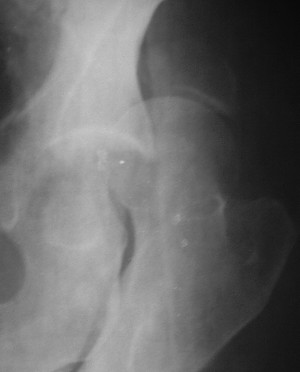

Два месяца нагрузки без костылей 19/12/03

Еще месяц 20/02/04

Больной 18 мая 2003 года в автоаварии получил перелом левой вертлужной впадины, вывих бедра. Госпитализирован в один из стационаров области.Вывих вправлен. В последствии бедро вывихивалось еще дважды. На консультацию был представлен снимок от 19.05.03г., больной переведен к нам 3.06.03г. Снимок при поступлении - перелом впадины, задне-верхний вывих бедра. 05.06.2003 г. выполнено открытое вправление вывиха левого бедра и остеосинтез стенки вертлужной впадины двумя винтами. Послеоперационный период без осложнений. Объем движений в левом тазобедренном суставе восстановился полностью. Выписан на амбулаторное лечение в удовлетворительном состоянии с рекомендациями 3 месяца ходить на костылях без нагрузки на оперированную конечность. На контрольных рентгенограммах левого тазобедренного сустава 13.10.2003 г. - признаки консолидации перелома; плотность, форма головки и состояние суставных поверхностей удовлетворительные. Разрешена дозированная осевая нагрузка, на конечность с использованием дополнительной опоры. 19.12.2003 г. больной обратился с жалобами на боли в левом тазобедренном суставе. На рентгенограммах левого тазобедренного сустава 19.12.2003 г., 20.02.04г. - асептичекий некроз головки бедра. 5.04.04г. - эндопротез. Сейчас ходит без трости, не хромает. Особенность эндопротезирования - при удалении винтов прослежена линия перелома заднего края впадины и предложено установить чашку несколько меньшего диаметра, чтобы она была покрыта несломанной частью.